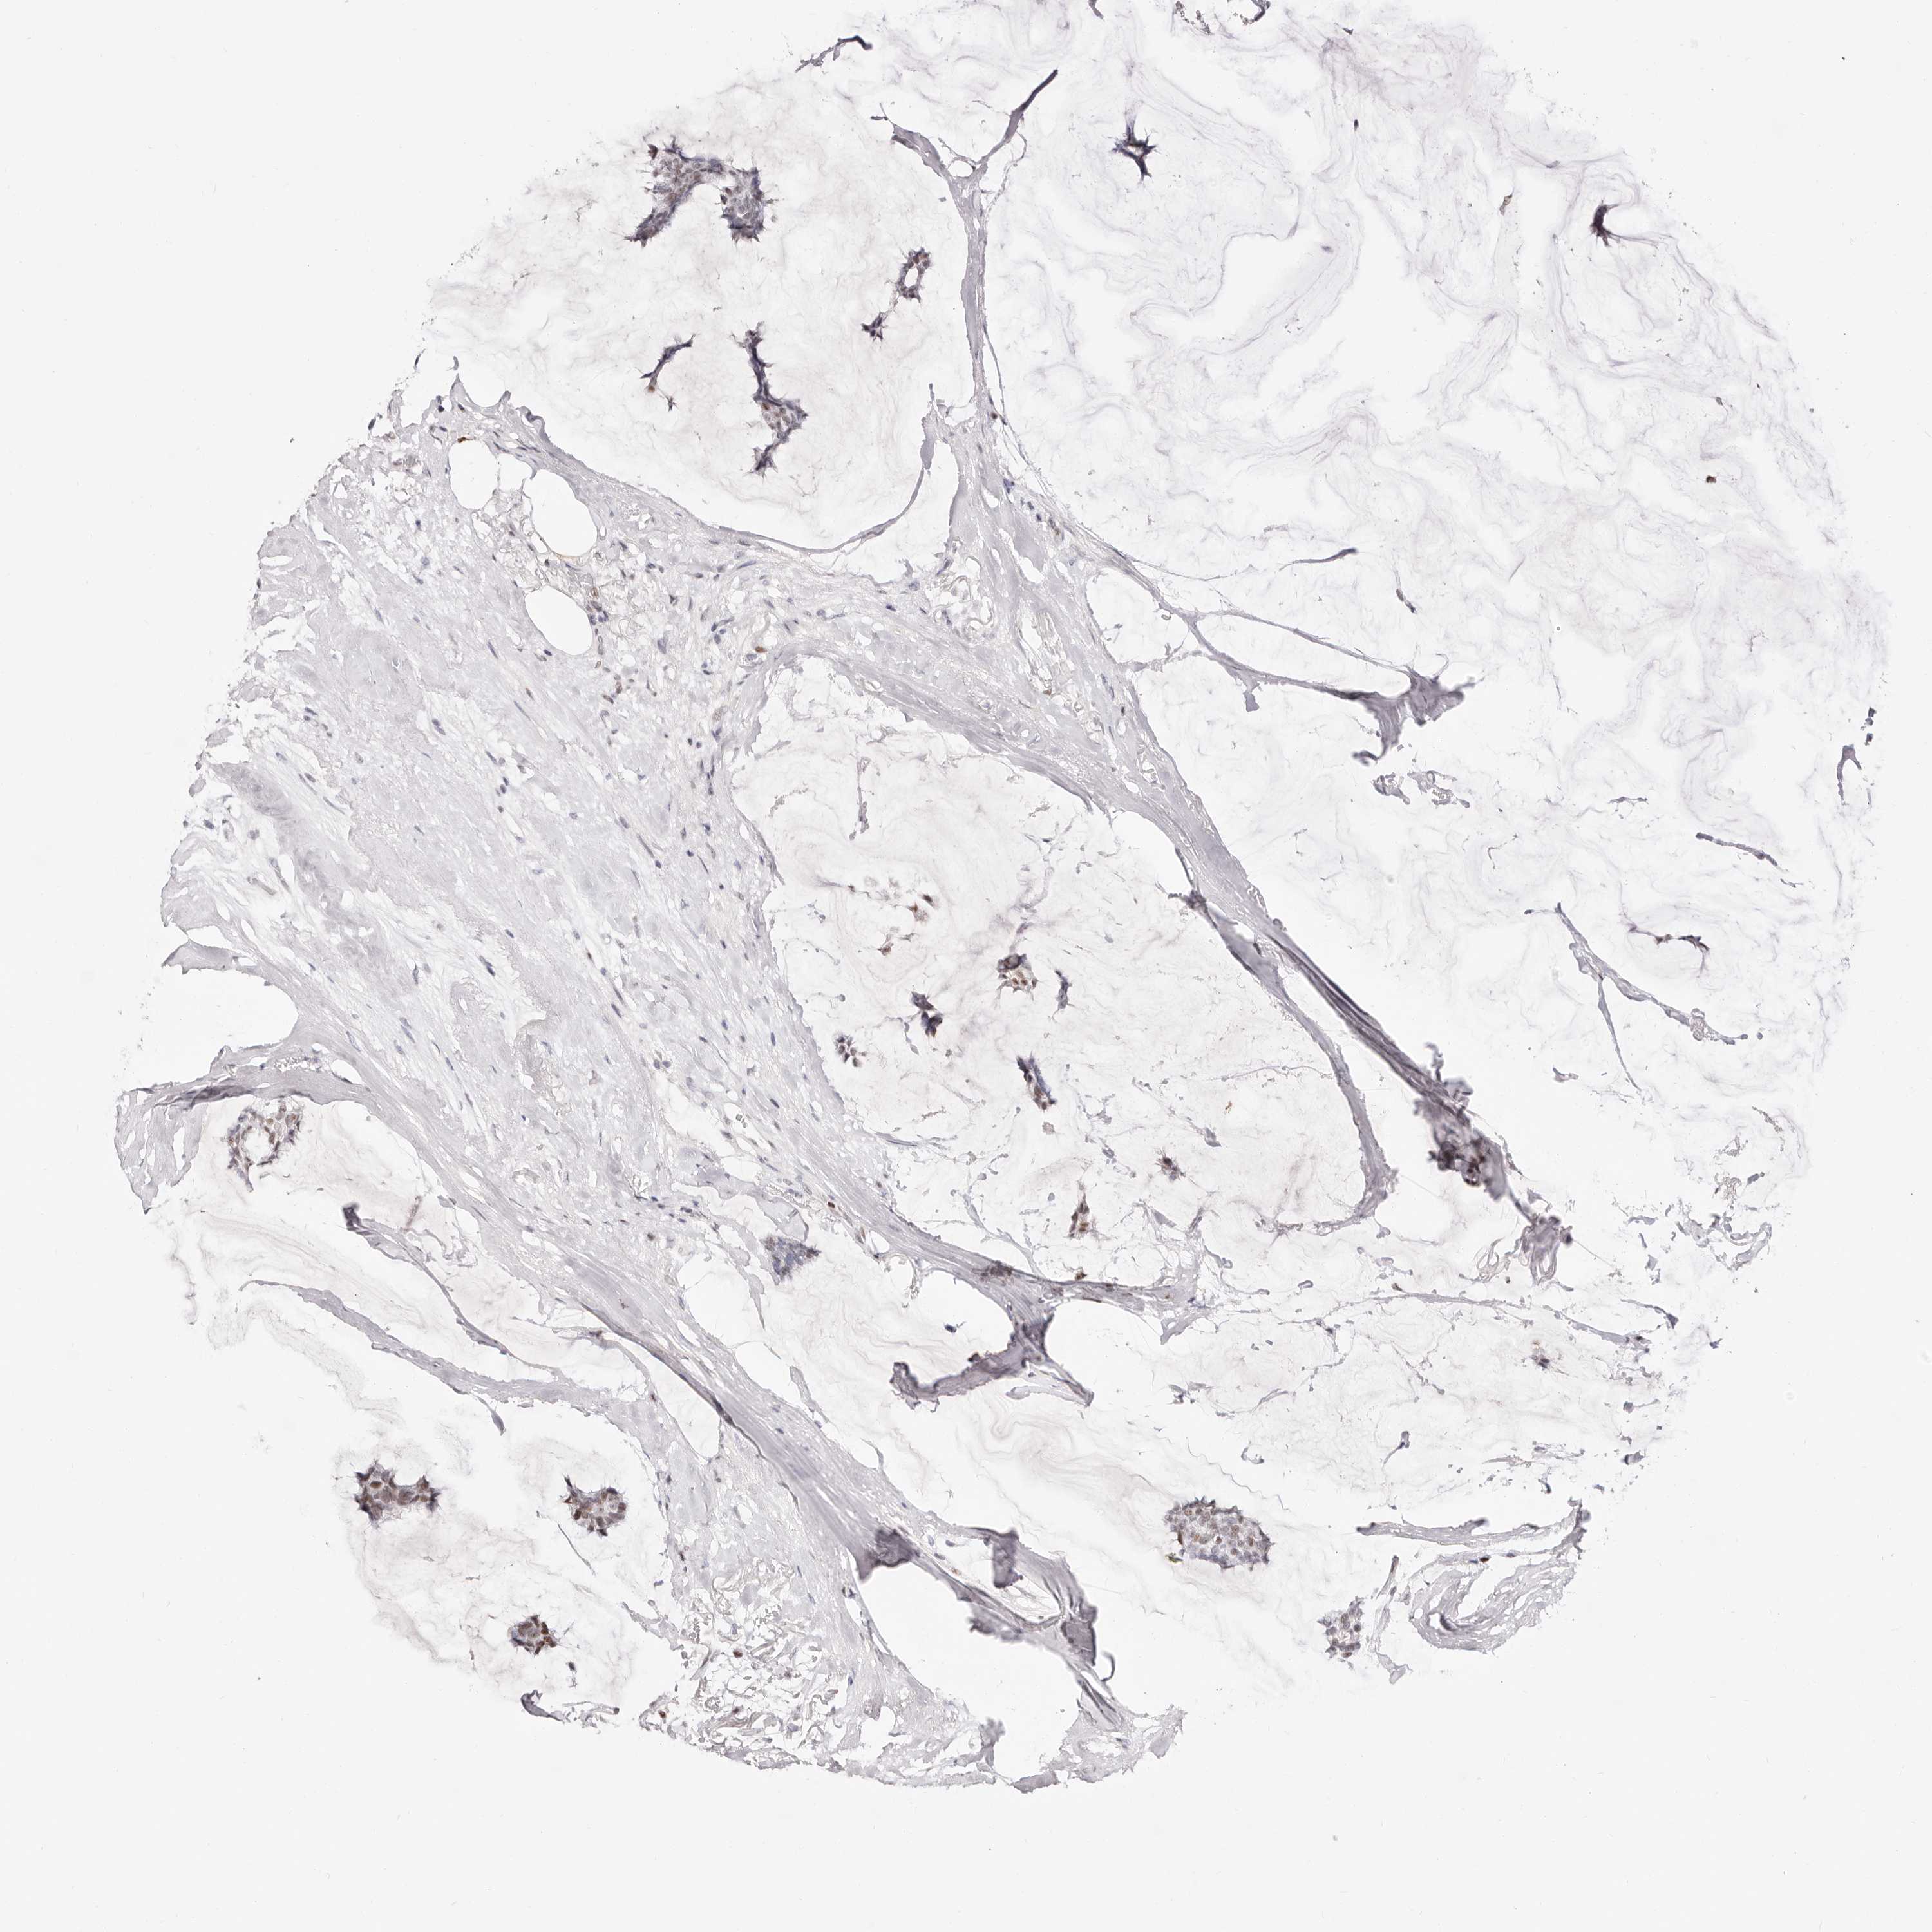

BRCA TCGA BRCA VALIDATION PROTEIN EXPRESSION